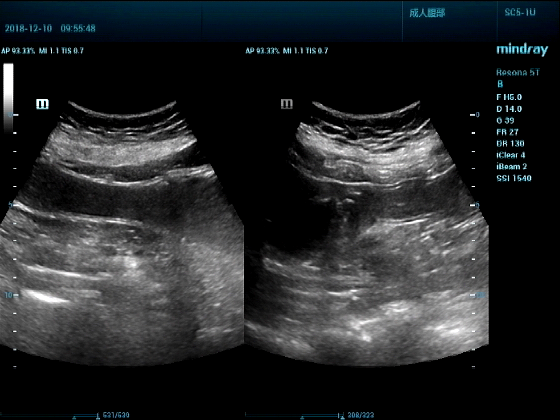

病例一:女,53岁,胃部不适一周来诊

超声可见:胃腔内见一小鸡蛋大强回声团块,后方伴强声影,位置活动。

问及病史吃山楂,柿子。

超声提示:结合临床考虑胃结石,治疗后复查

女,53岁,胃部不适一周来诊